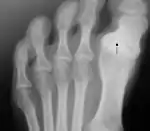

Radiografía de un pie derecho en vista dorsal que muestra los huesos del dedo gordo. El ligamento de Lisfranc está situado en la marca roja de la esquina superior izquierda, y el borde inferior del dedo se destaca con una línea verde.

Anatómicamente forma parte de una cadena osteo-articular de tres piezas que prolonga el arco medial del pie partiendo de la primera cuña, el llamado «primer radio plantar». Sus componentes óseos parten del primer metatarsiano, y cuenta con solo dos falanges—siendo la falange media o segunda falange la que está ausente—[13] unidas mediante una articulación en pivote o trocoide, en tanto que el resto de dedos cuentan con tres. En la conexión metatarsiano-falange se encuentra el sistema glenosesamoideo, del que no disponen el resto de los dedos, y que está formado por dos huesos sesamoideos, que actúan a modo de polea (mecanismo sesamoideo) ayudando a los tendones de los músculos del dedo gordo en su función.[14] El sistema está formado por el cartílago glenoideo, que amplía la cavidad articular de la falange, y los dos huesos sesamoideos unidos por el ligamento intersesamoideo.[15]

También encontramos el ligamento de Lisfranc entre la base de la primera cuña y la cara interna de la base del segundo metatarsiano. Todos los dedos del pie poseen ligamentos intermetatarsianos que unen sus bases, salvo el dedo gordo con el segundo, el cual solo está unido a la cuña. Esto permite individualizar los desplazamientos, que en el resto de los dedos suceden en bloque debido a los ligamentos intermetatarsianos.[16]